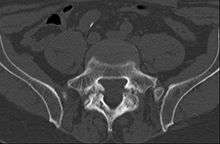

Computed Tomography

Commonly known as a CT Scan or CAT scan, this form of imaging is very similar to x-ray technology but produces many more images than an x-ray does. The multiple images produce cross-sectional views not possible with an x-ray. This allows a physician or radiologist to examine the images from many more angles than an x-ray allows. For this reason the CT scan is much more accurate in detecting spondylolysis than an x-ray. Bone scintigraphy combined with CT scan is considered the gold standard which means that it is best at detecting spondylolysis.[12][14]